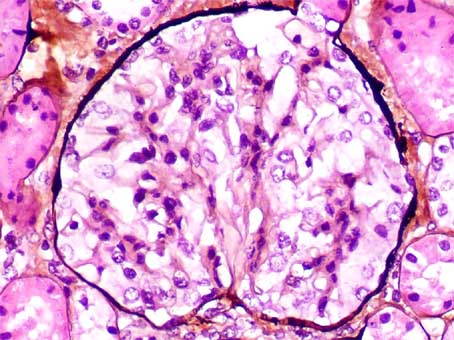

Figure 1.

First biopsy. H&E; left, X200; right, X400.